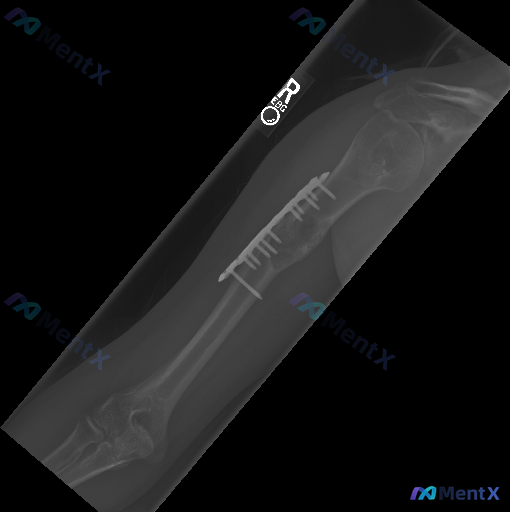

整理到一张右侧肱骨的正位X光片,先给大家同步一下客观的影像表现: 1. 骨骼结构:右侧肱骨干中段皮质连续性中断,存在明显的大段骨质缺损;缺损边缘有不同程度的硬化或退缩,目前看不到明确的骨痂连接。 2. 固定装置:可见外固定架,近端钢针穿过肱骨近端,远端钢针固定于肱骨髁上区域,中间有长杆连接,维持了肱...